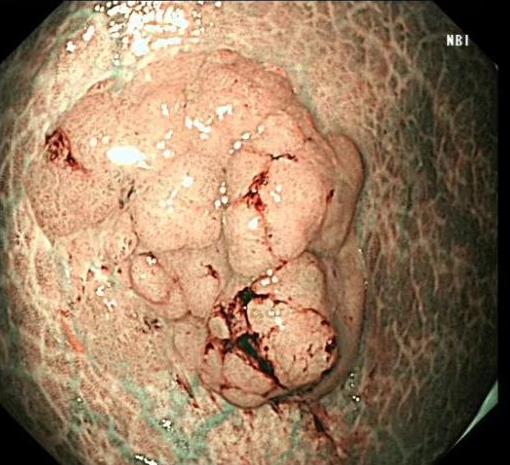

• 色素内镜和窄带成像技术联合放大内镜对早期结直肠癌及癌前病变的诊断价值研究

摘要:目的 探究色素内镜(CE)和窄带成像技术(NBI)联合放大内镜(ME)对早期结直肠癌及癌前病变的诊断价值研究。方法 选取2023年8月-2024年7月于该院接受检查的疑似早期结直肠癌及癌前病变的患者160例。采用四格表法,分析NBI-ME和CE-ME检测早期结直肠癌及癌前病变的敏感度、特异度和准确度;采用Kappa一致性检验,分析CE-ME和NBI-ME诊断早期结直肠癌及癌前病变与病理检查的一致性。结果 病理结果显示,良性病变52例,癌前病变90例,结直肠癌18例。CE-ME检测结果显示,良性病变43例,癌前病变101例,结直肠癌16例,漏诊率为33.33%;CE-ME诊断早期结直肠癌及癌前病变与病理检查的一致性中度(Kappa = 0.605,P < 0.01),敏感度为66.67%,特异度为97.18%,准确度为93.75%。NBI-ME检查结果显示,良性病变43例,癌前病变100例,结直肠癌17例,漏诊率为16.67%,NBI-ME诊断早期结直肠癌及癌前病变与病理检查的一致性较高(Kappa = 0.714,P < 0.01),敏感度为88.33%,特异度为98.59%,准确度为96.88%。CE-ME与NBI-ME两者联合检查结果显示,良性病变56例,癌前病变86例,结直肠癌18例,漏诊率为5.56%,两者联合诊断早期结直肠癌及癌前病变与病理检查的一致性极高(Kappa = 0.857,P < 0.01),敏感度为94.44%,特异度为99.30%,准确度为98.75%,高于CE-ME和NBI-ME单独检查。结论 CE和NBI联合ME对早期结直肠癌及癌前病变具有较高的诊断价值。值得应用于临床。